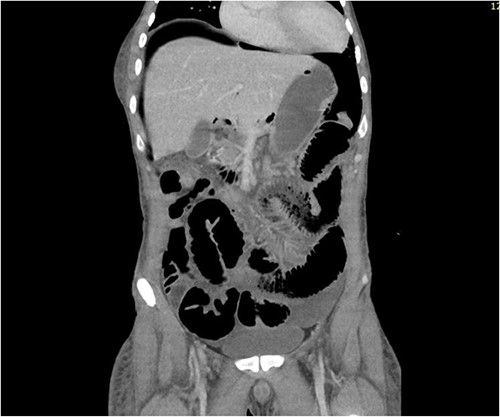

CT abdomen revealed a large amount of free air throughout the abdomen, mostly localized anterior, but also perihepatic, perigastric, paracolic, and perisplenic (Figs 1 and 2).

CT abdomen showing large amount of free air throughout the abdomen.